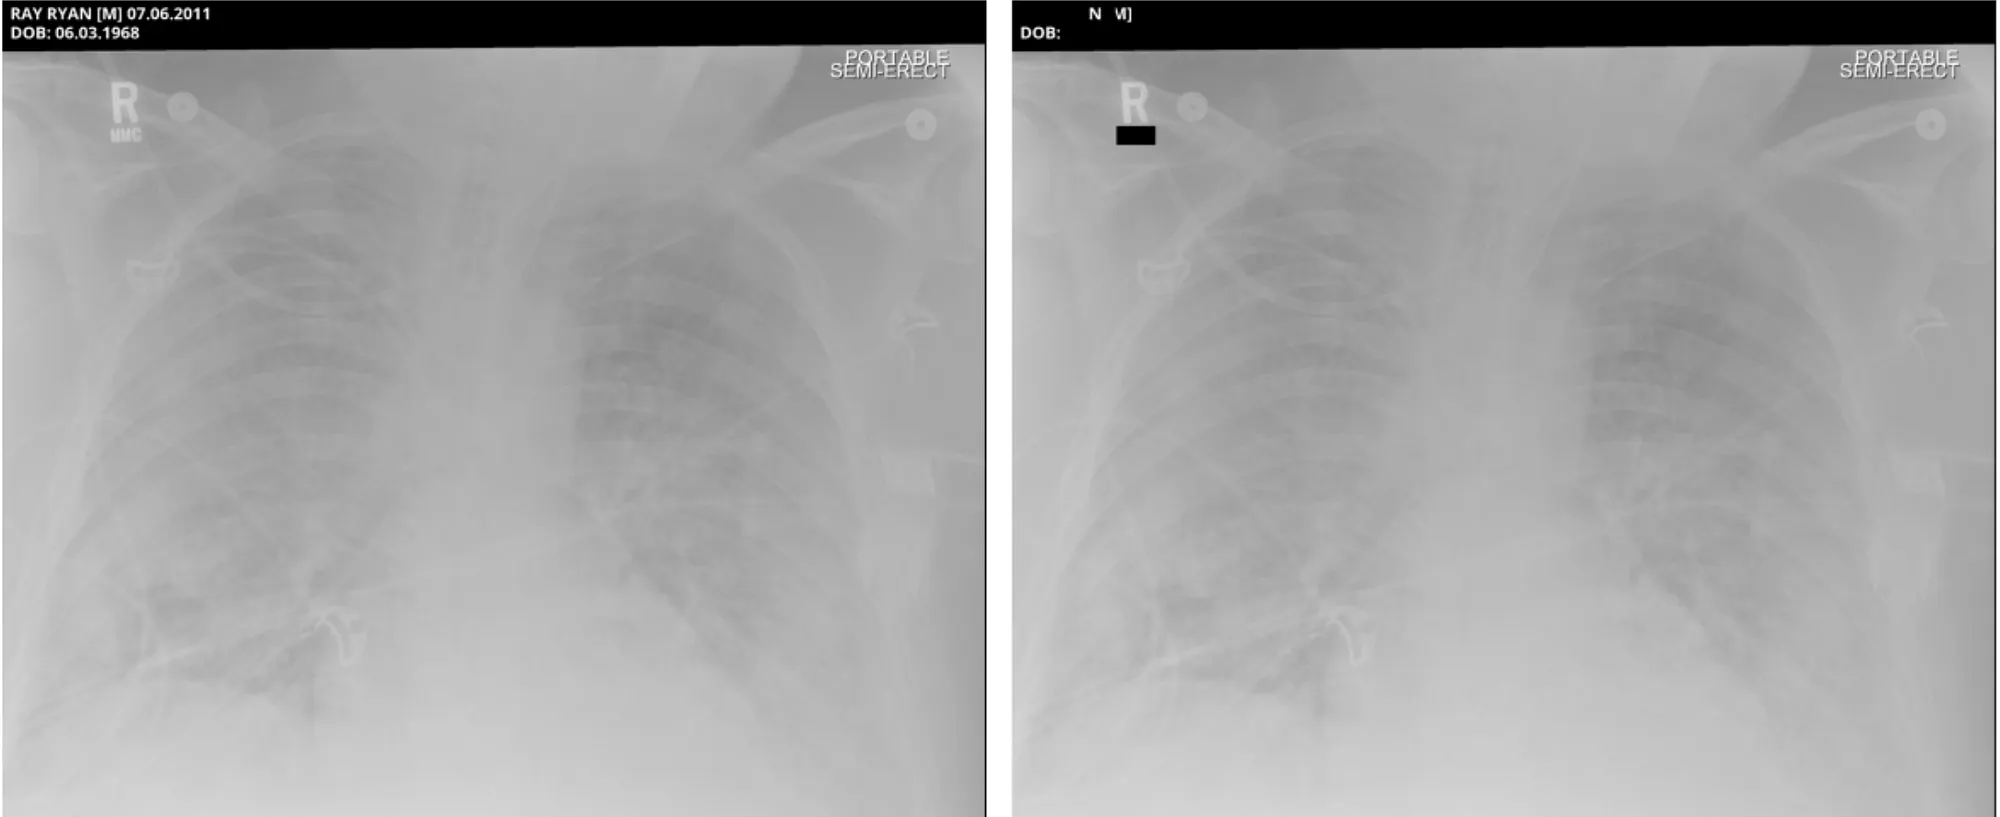

Pixel DeIdentification Original ( Left ) -> DeIdentified ( Right )

Reference : MIDI-B Pixel Metadata DeIdentification Notebook

Metadata DeIdentification Original ( Left ) -> DeIdentified ( Right )

Sample Pixel Result 1

Sample Pixel Result 2

Sample Pixel Result 3